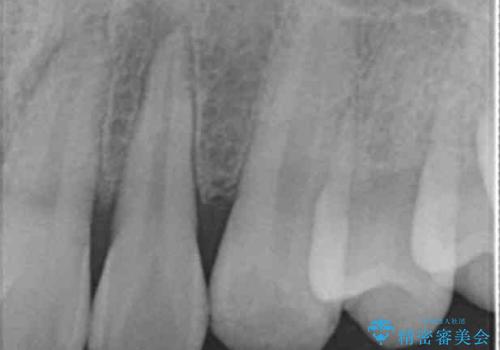

歯の神経の状態を見たところ、前歯3本とも神経が死んでしまっていました。

根の治療を行い、ぐらつきに関しては様子を見て連結をするとのお話をさせていただきました。